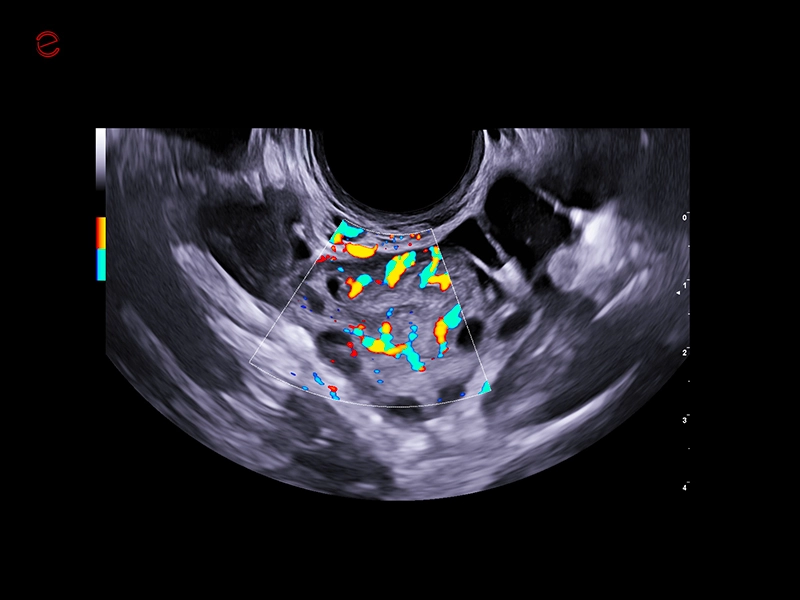

IDEAL FOR A VARIETY OF CLINICAL APPLICATIONS

High-quality imaging on-the-go

A compact and dependable partner, the MyLab™C25 is designed to support your daily practice with ease, providing high-quality imaging for confident diagnostics every time. With MyLab™C25 and its wide range of probes, we provide you with the ability to perform examinations in a broad variety of clinical applications such as general imaging, superficial scanning, cardiology, vascular, gynecology and obstetrics